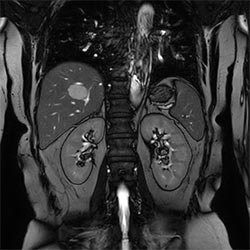

In a society where reimbursements are declining and chronic conditions lead to increased MR procedures and longer waiting times, there is ever increasing pressure on the radiology department. Today, further attempts to accelerate, compromise image quality or are limited to a narrow range of scans. Therefore, to meet the increased demand for productivity, a technology break-through in acceleration is still required. Leveraging our long standing leadership position in speed (i.e. SENSE), Philips brings compressed SENSE, a breakthrough in productivity.

Learn more about the main principles of Compressed SENSE and how it introduces a paradigm shift in productivity, how Compressed SENSE was designed around image quality, and how it advances productivity for clinical MR imaging.

Read about the experiences from Kantonsspital Winterthur (Switzerland) who experienced Compressed SENSE to be a simple yet powerful way to accelerate MRI scanning for different contrast types and sequences, in 2D as well as 3D.